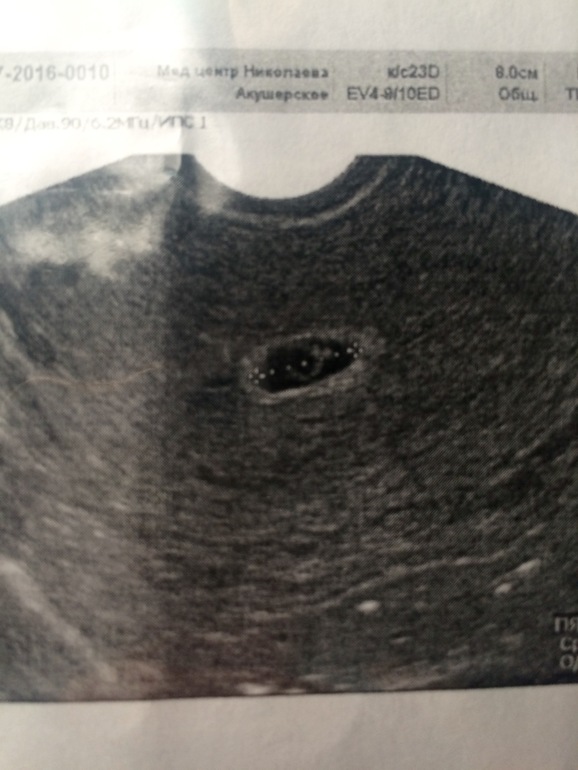

ФолликулометрияНу вот и дошла я до УЗИ . Срок немного не совпадает с месячными, овуляция была поздняя , по М 7-8 недель , по узи 5-6 недель. Прекратилась моя лапочка по середине матки, плодное яйцо - 10 мм ( на 5,1 нед. ). Эмбрион один, КРТ -2,2 мм ( 5,5 нед) Сердечко бьётся, Желточный мешочек 2,9 мм. Шейка матки 37 мм, зев закрыт .

Вообщем получила я массу удовольствия посмотрев как бьётся сердечко моей крошечки , и эмбриончик она мне увеличила , вроде бы не первая беременность а всё равно чювство как в первый раз !!! Ну и конечно наше первое фото))